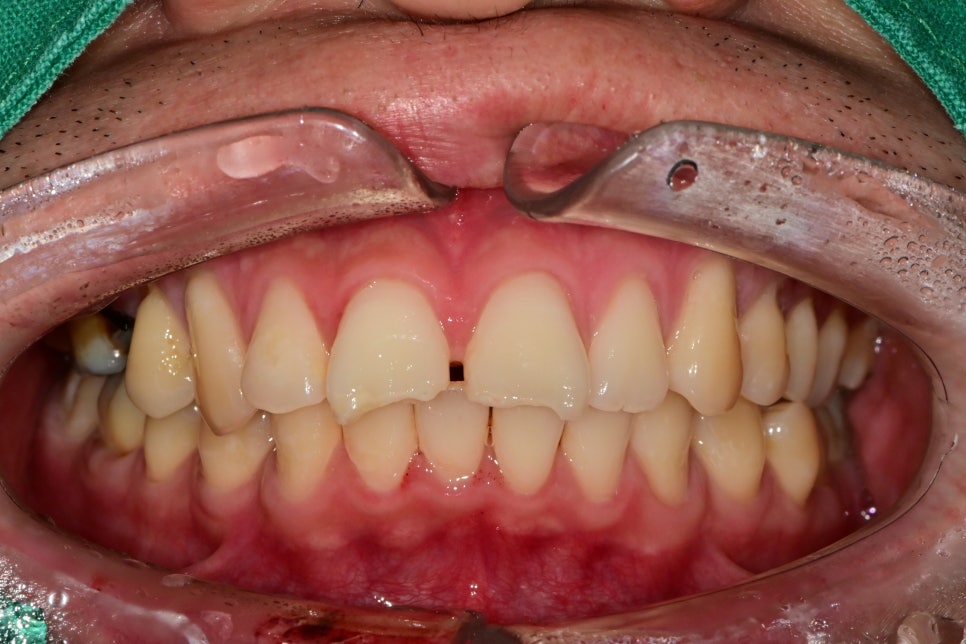

첫 번째 환자분은 넘어지시면서 아랫입술의 상처를 동반한 정중앙의 정중치의 파절로 내원하셨습니다.

치아에 충격이 전해졌기 때문에 미세한 통증은 있었지만 엑스레이상에서 파절선이나 동요도는 보이지 않았습니다.

증상을 지켜보는 동안 깨진부위를 채우기 위해 레진 치료를 선행하였습니다.

치아 사이 벌어짐은 원래 벌어진 치아였지만 깨진 부분을 치료하면서 같이 공간까지 치료했습니다.

첫날 급한 처치만 우선적으로 했기 때문에 신경의 괴사나 추후 통증은 체크하기로 했으며 비교적 간단하게 치료가 마무리되었습니다.

추후 치아 형태를 복원하기 위해 라미네이트나 크라운 같은 보철이 필요할 수도 있지만

현재 레진으로도 충분히 지낼 수 있기 때문에 체크 시 좀 더 심미적으로 다듬는 과정을 통해 지내시기로 했습니다.